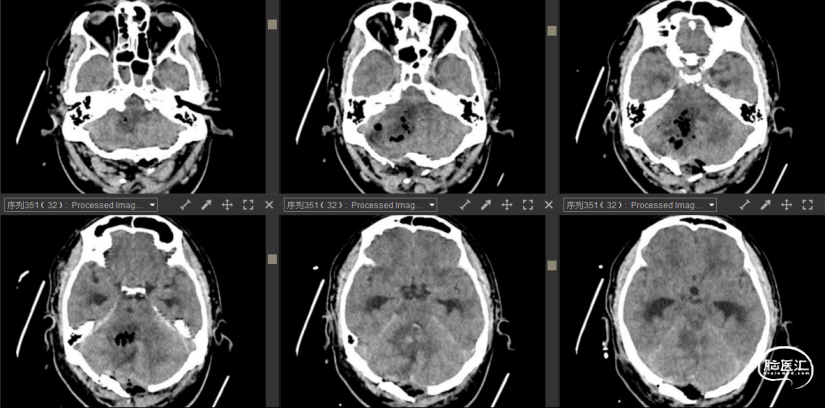

检查:2022-11-01我院头颅CT示:右侧小脑脑出血,脑实质出血量约21ml,少量蛛网膜下腔出血。胸部CT示:右肺中叶内侧段、下叶、左肺上叶下舌段、下叶后基底段感染。

诊断:1. 右侧小脑出血;2. 梗阻性脑积水;3. 少量蛛网膜下出血;4. 高血压病3级(极高危);5. 肺部感染。

2022-11-01头颅CT及CTA

2022-11-01术后头颅CT

2022-11-05头颅CT

2022-11-17头颅CT